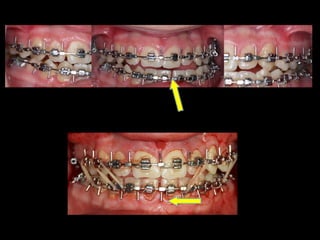

Anquilosis ATM Hiperplasia condílea Cirugía ortognática

Modelos estereolitográficos  SAHS moderado Hipoplasia maxilar

Anquilosis ATM Hiperplasiacondílea Cirugía ortognática